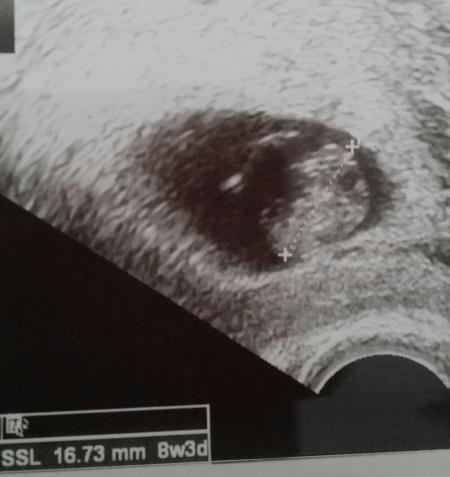

Ich daaaaaaaanke euch für's Daumen drücken. es ist alles in Ordnung als ich meinen Babykrümmel sah, musste ich direkt weinen. Meine Frauenärztin hat fast mitgeweint. wir haben uns erstmal be gefühlte Minute gedrückt. und ich wurde 5 Tage vorgestuft. das Herzchen hat schön geschlagen und es ist schon so groß geworden. Mensch , jede Schwangerschaft ist echt immer was anderes und immer wieder alles aufregend als wenn es die erste sei. bei mir zumindest also bin ich heute 8+3. und das kleine ist 16,73 mm LG

achso... hier noch ein Bildchen